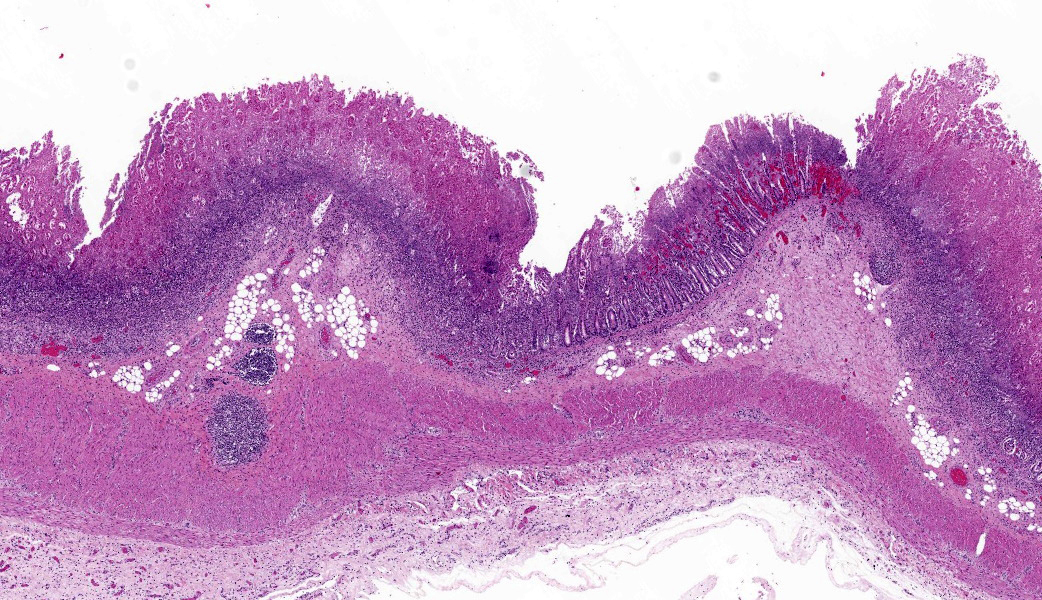

Microscopic Description:Large intestine (Colon ascendens): Multifocal to coalescing, a thick layer of fibrin, sometimes intermingled with degenerated neutrophils, and abundant coccoid to rod-shaped bacteria are attached to the mucosa. In these areas, the mucosa is diffusely destroyed (necrosis) and replaced by fibrin, cell debris and fewer coccoid to rod-shaped bacteria. The lamina propria and the submucosa show a moderate infiltration with neutrophils as well as fewer lymphocytes and histiocytes. The few remaining crypts are dilated and some of them contain neutrophils and cell debris. Some capillaries and venules contain fibrin thrombi or are dilated and filled with neutrophils.

- Colon: Colitis, necrotizing, subacute, diffuse, severe, with Peyer?s patch depletion and numerous coccobacilli.

Due to the degree of necrosis and inflammationin the submitted section of colon. some participants had difficulty deciding in which segment of the GI tract this sample originated. The presence of occasional intact crypts and multiple lymphoid follicles were helpful in establishing an anatomic location of ?intestine? (remember, there are no lymphoid follicles in the stomach except in severe cases of Helicobacter spp infection in some species), but it can be challenging to get further than ?intestine? when a section is as inflamed and necrotic as the tissue is in this case.